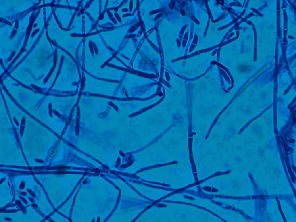

Introduction: We describe a unique case of sclerouveitis that progressed to endogenous Fusarium endophthalmitis in a 69-year-old male with chronic lymphocytic leukemia (CLL). We highlight the risk of treating sclerouveitis with oral corticosteroids, which can exacerbate an infection and contribute to disease progression. Case Presentation: A 69-year-old male with CLL on zanubrutinib, a second-generation Bruton's tyrosine kinase inhibitor, was admitted to the hospital for osteomyelitis of the left foot. At presentation, the patient also reported right eye pain for 1 week and vision loss over the course of 1 month. Vision in the right eye was hand motion. Slit lamp examination revealed scleral inflammation in the right eye with violaceous injection, chemosis, inflammation in the anterior chamber, and diffuse subconjunctival hemorrhage. There was significant corneal edema preventing fundus examination. B-scan ultrasonography demonstrated a flat retina with no vitritis or scleral thickening. Forty-eight hours after treatment with oral and topical corticosteroids, the patient's eye pain improved but his vision worsened. Repeat B-scan showed new-onset vitritis. Fungal culture obtained by diagnostic pars plana vitrectomy (PPV) revealed growth of Fusarium. The patient was treated with oral and intravitreal voriconazole in addition to intravenous voriconazole and amphotericin B for systemic therapy. Corticosteroids were discontinued. Despite aggressive therapy, the patient's disposition declined to the point of transitioning to comfort-focused care, and he passed away. Conclusion: Endogenous fungal endophthalmitis is most commonly seen in immunocompromised patients, and oral corticosteroid therapy for such patients should be used with caution as it can worsen an infection. In cases of fusarial endophthalmitis, visual prognosis is poor.